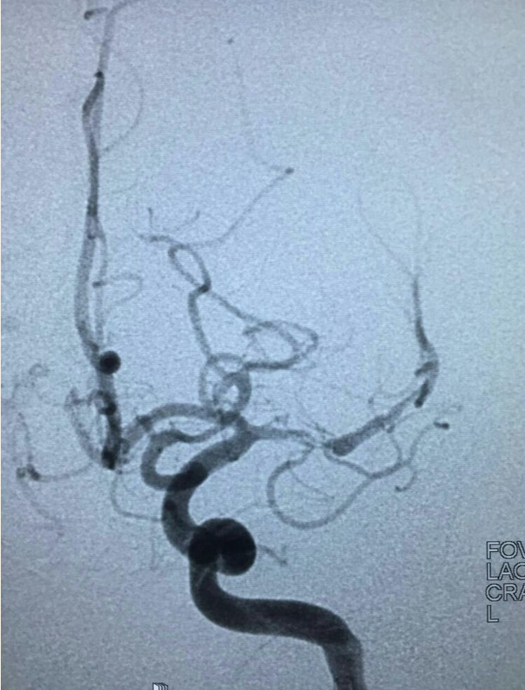

出院1月后再次出现右侧肢体无力,并反应迟钝,行脑血管造影见左侧大脑中动脉重度狭窄。

给予双抗(氯吡格雷联合阿司匹林)治疗3周,症状无明显改善,复查造影见左大脑中远端血流较前明显变差。